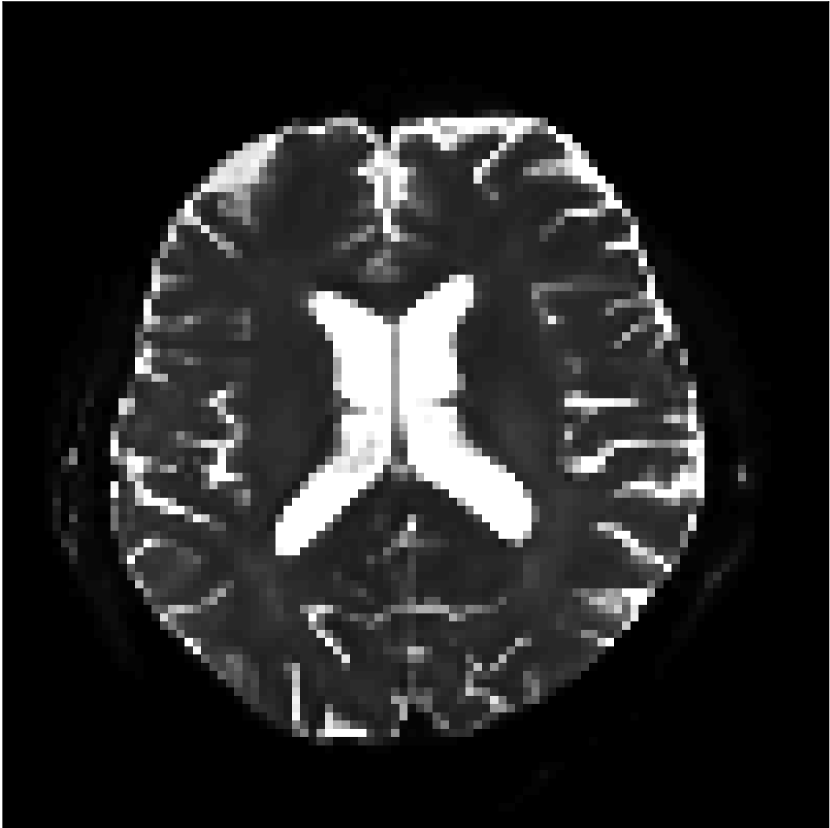

Figure 9 shows parameter maps for the different methods without partial Fourier (No PF) and with 5/8ths partial Fourier (5/8 PF). Mean diffusivities calculated from the raw DWI data (Raw) show notable noise and Gibbs ringing artifacts, while this is substantially removed with the state-of-the-art (SoA) method. However, the state-of-the-art method begins to lose its ability to compensate for the Gibbs ringing and resolution loss when partial Fourier is utilized in the acquisition. The effects of partial Fourier increases are primarily evident in the enlargement of the lateral ventricles and the presence of black lines in the vicinity of the lateral ventricles. The MCNN model is able to compensate somewhat for the ringing effects, but begins to introduce substantial artifacts at the 5/8ths partial Fourier factor, whereas the CCNN model continues to give high-quality mean parameter maps across all PF factors.

Raw

SoA

MCNN

Standard PF

CCNN

b=0𝑏0b=0 s/mm2

No PF

5/8 PF

FA

MK

Figure 9: Parameter maps from various methods (with CSF masks for FA and MK). At the top are shown the b=0𝑏0b=0 images from Raw, state-of-the-art (SoA), MCNN, standard partial Fourier, and CCNN methods. Rows 2 and 3 show results for mean diffusivity, rows 4 and 5 show results for fractional anisotropy, and rows 6 and 7 show results for mean kurtosis. The SoA method and both deep learning methods perform well without partial Fourier acceleration; however, at the 5/8ths partial Fourier factor, substantial artifacts are present for all methods other than the CCNN method.

Similar trends are observed in the other diffusion parameter maps.